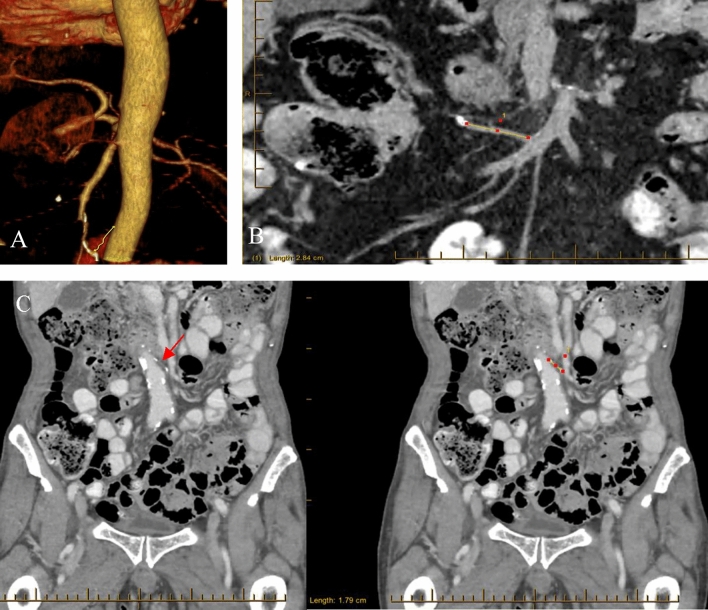

Methods: A prospective cohort study at Concord Hospital was conducted on anterior resection (AR) or right hemicolectomy (RH) patients with stage I to III CRC (1995-2019). Using surveillance computed tomography (CT), RAPL of the inferior mesenteric artery (IMA) or ileo-colic artery (ICA) pedicle was measured independently by two observers. The intra-class correlation coefficient assessed the reproducibility of the measurements. Kaplan-Meier and univariate Cox regression analyses estimated overall survival (OS) and disease-free survival (DFS), while univariate and multivariate linear regression models tested correlations between RAPL and clinicopathological features.